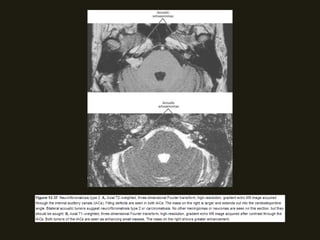

SCHWANOMAS ACÚSTICOS

• Tumores benignos do VIII PC ocorrem no CAI/ângulo

as de Schwann; Associação com neurofibromatose tipo 2;

• RM método de escolha (nervo espessado e com realce pelo

pequenos dos nervos normais;

• Podem ser massas pequenos ou grandes;

hidrocefalia e compressão do IV ventrículo;

acusticus e cápsula óptica; Assimetria dos CAI > 2mm sugere

NEOPLASIAS BENIGNAS SCHWANOMAS ACÚSTICOS • Tumores benignos do VIII PC ocorrem no CAI/ângulo cerebelopontino, surgindo na junção das células da glia com as de Schwann; Associação com neurofibromatose tipo 2; • Sintomas dependem da localização do tumor (há compressão dos nervos coclear e vestibular (CAI) – zumbido, diminuição acuidade auditiva; • RM método de escolha (nervo espessado e com realce pelo contraste; podem ser císticos;); diferencia schwanomas pequenos dos nervos normais;

NEOPLASIAS BENIGNAS • Podemser massas pequenos ou grandes; • Grandes – distorção da fossa posterior; hérnia de tronco, hidrocefalia e compressão do IV ventrículo; • TC alta resolução – mostras alterações ósseas do CAI, porus acusticus e cápsula óptica; Assimetria dos CAI > 2mm sugere MASSA!!